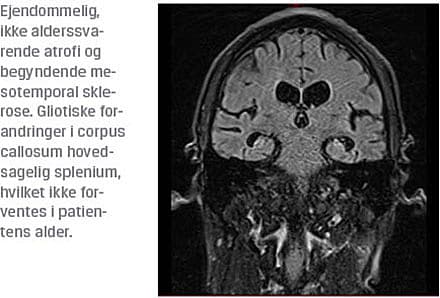

Efter tre måneders indlæggelse sås yderligere tab

af kognitive funktioner på trods af seponering af antipsykotika. Der var altså fortsat manglende diagnostisk afklaring, og der blev rejst mistanke om en infektiøs/

inflammatorisk lidelse, hvorfor der blev foretaget en MR-skanning af cerebrum samt lumbalpunktur.